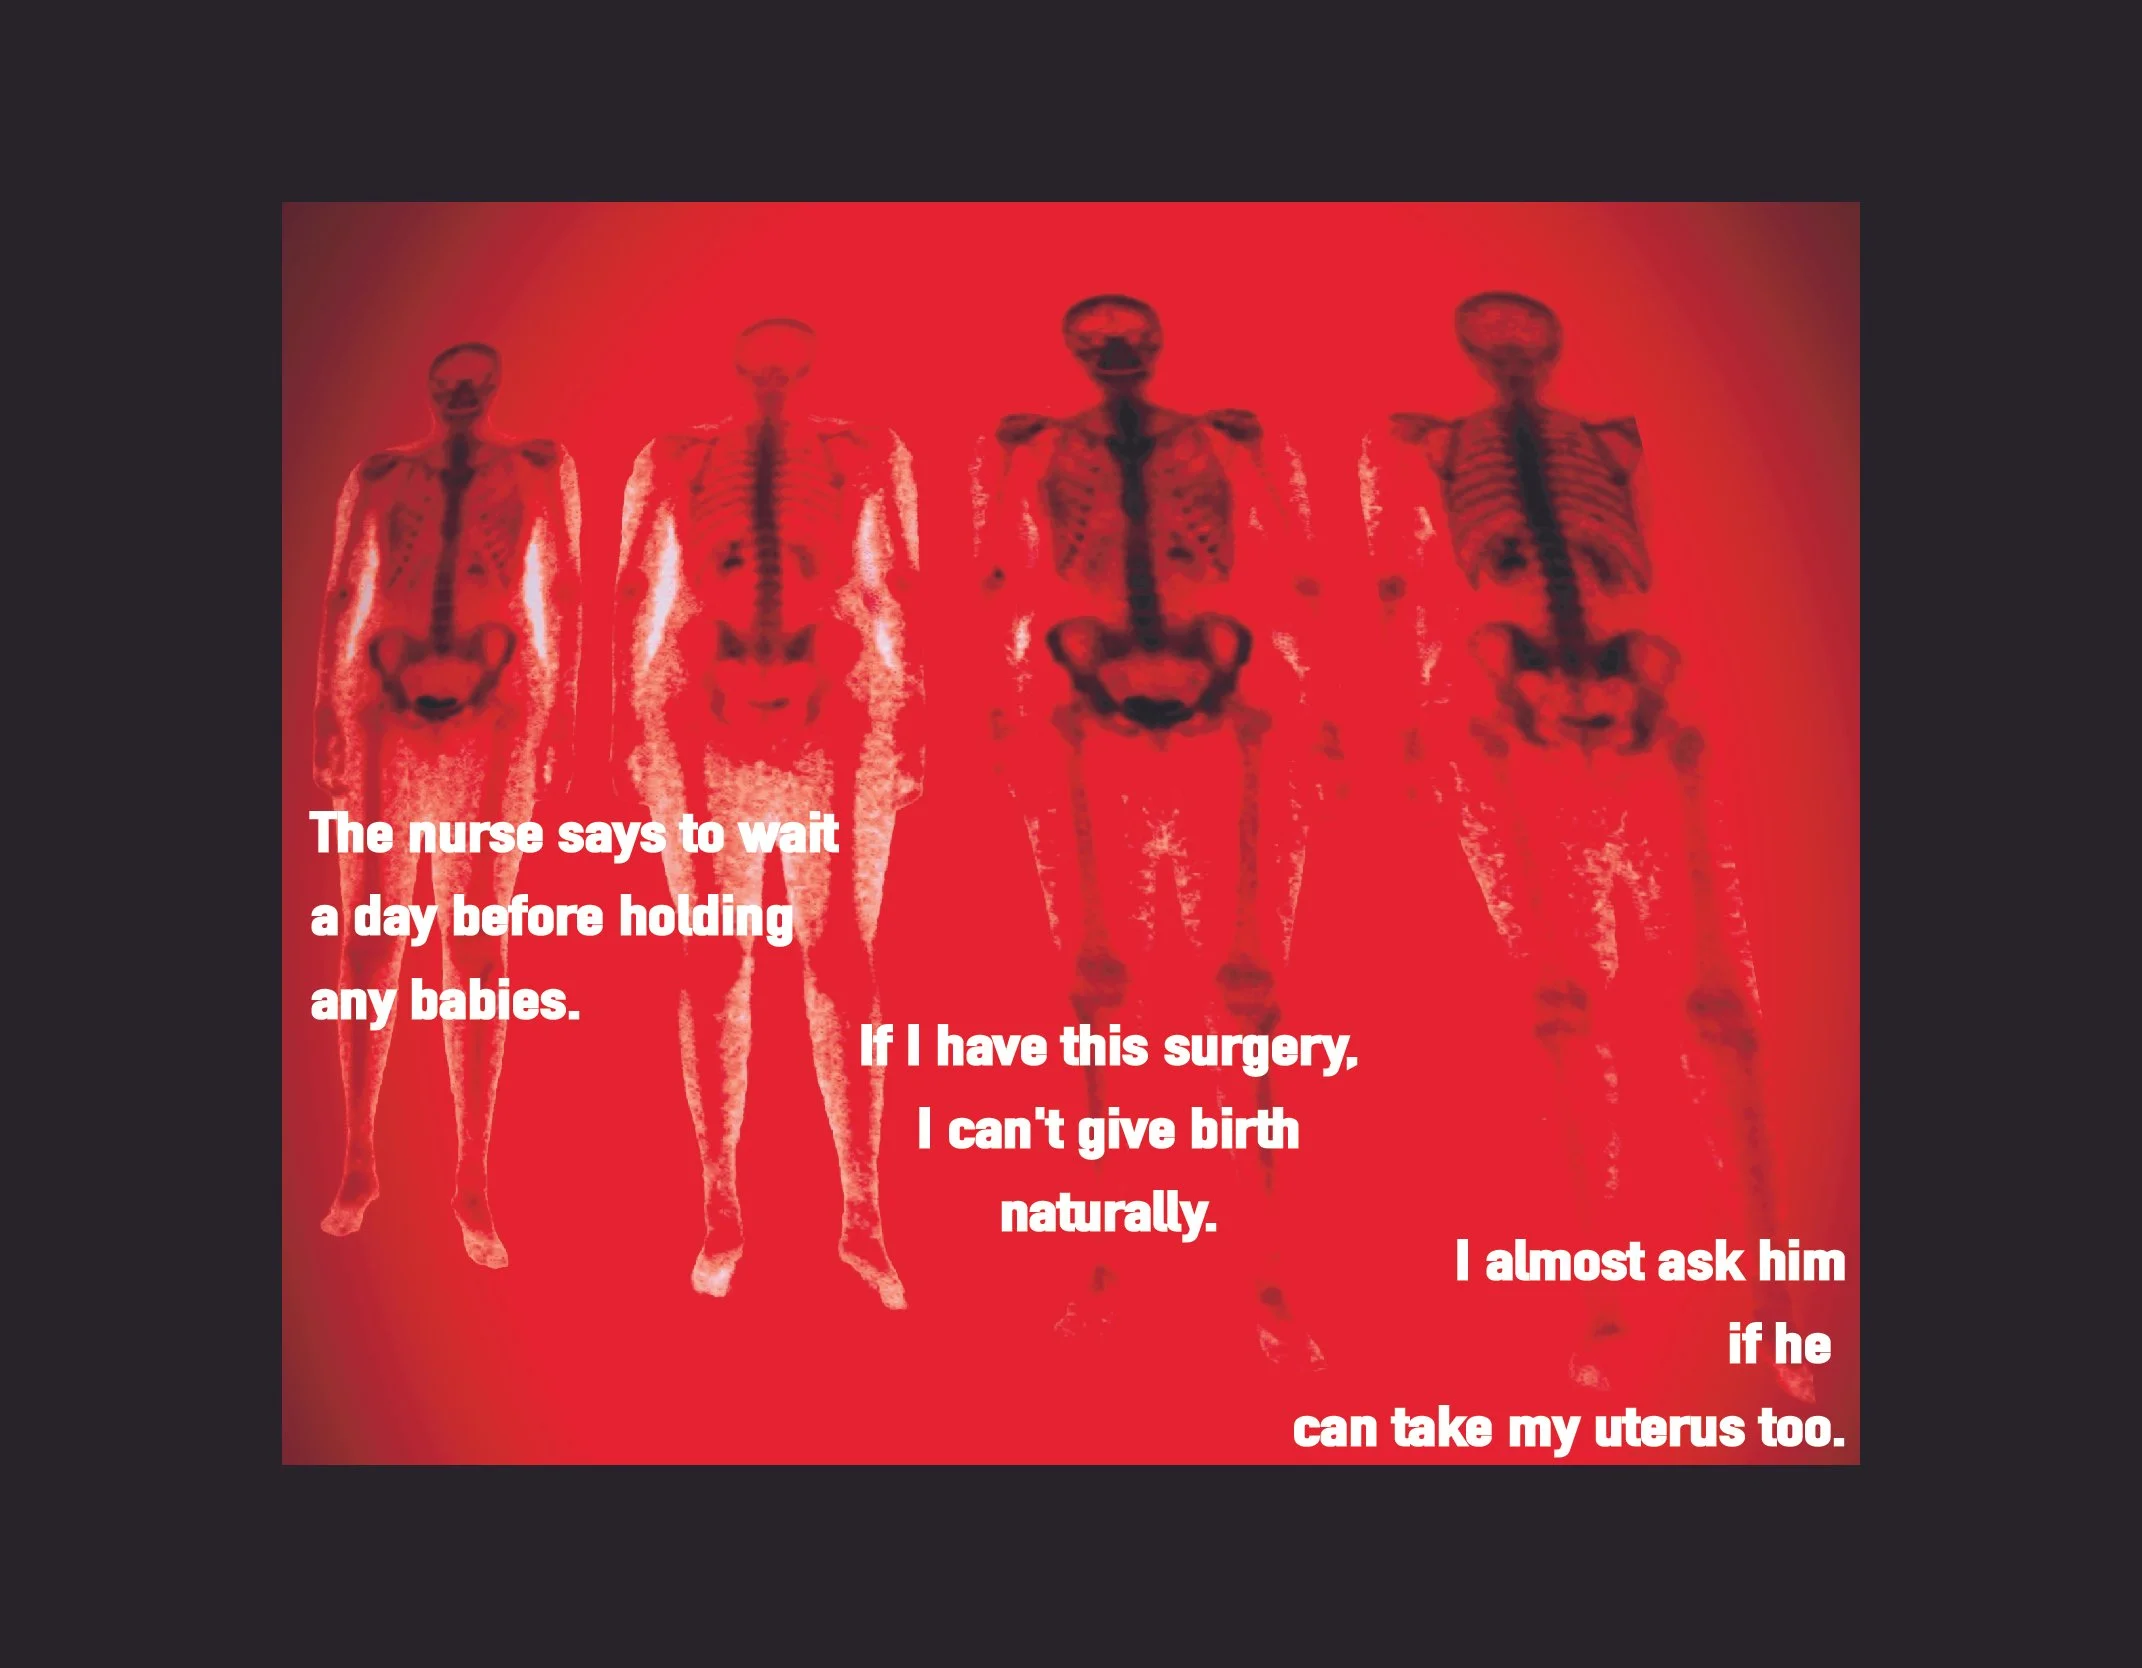

Confessions of a Bad-Backed Young Masc